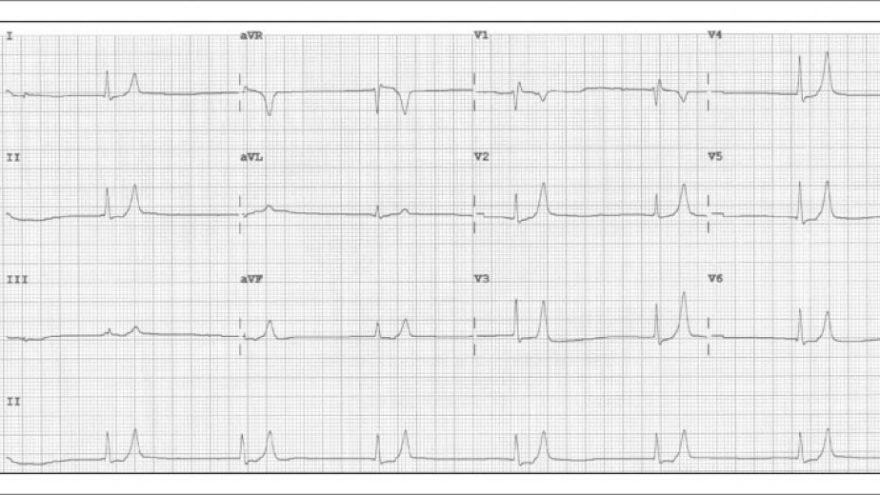

Figura 1: ECG solicitado na sala de emergência. Hipercalemia moderada: ritmo de escape juncional (perda da onda P) e apiculamento da onda T, com formato em tenda.